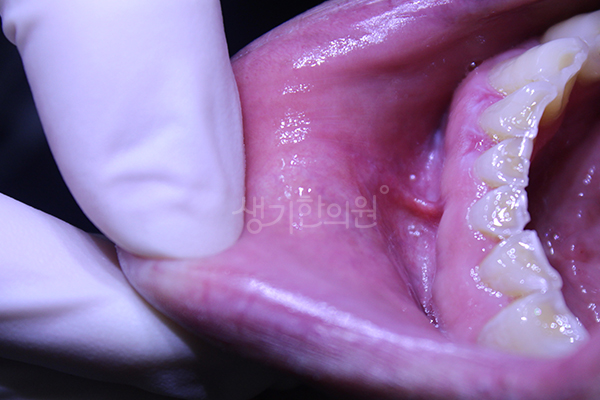

생기 치료 사례는 생기한의원 각 지점별 실제 치료 환자의 동의를 받아 공개하는 내용입니다.

생기 치료 사례는 동일인의 치료 전후 사진을 인위적 수정하지 않은 내용입니다.

각 환자의 상태와 특성에 따라 치료 효과에 차이가 있을 수 있고, 일반적 부작용이 나타날 수 있습니다.